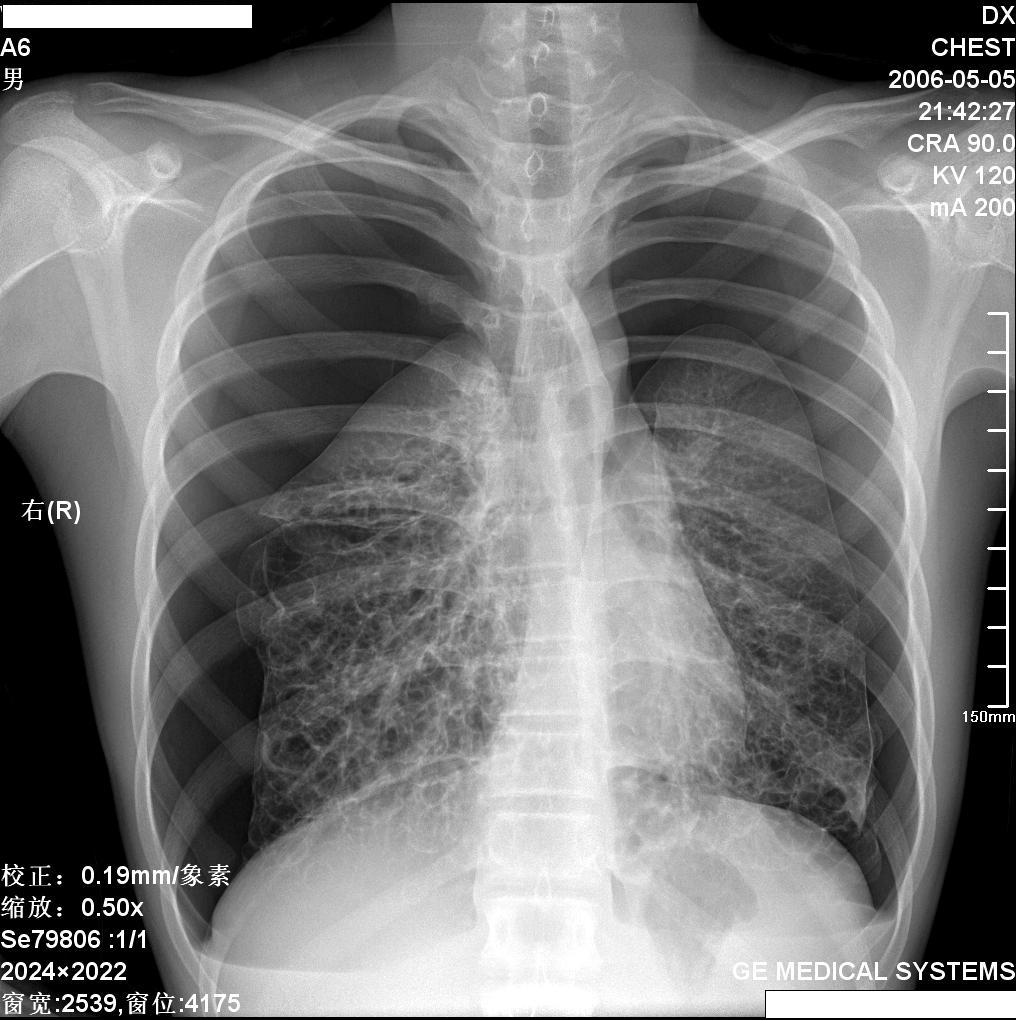

x:双肺中下野多发囊状卷发状影,壁模糊,无液平,双肺纹理强,-------印象:先天支扩并感染.

双肺纹理粗乱,双下肺见网囊小点结影,膈肌低位,颈部见皮下气肿征,侧位可疑纵隔气肿。男性,16岁,无相关病史可考虑1间质性肺炎。2慢支炎或支气管哮喘。3支扩及其他待排请提供病史

王某某,男,16岁,既往无经常咳嗽、咳痰、胸闷、发热史,活动与同龄儿童相似,三月前突感胸、颈前痛、无喘憋,查体胸骨上皮下气肿,双肺呼吸音对称。胸部dr及ct示纵隔气肿,双肺囊肿。近两月反复出现胸痛、喘憋,无发热、黄痰及痰血,呼吸音减低,胸部dr示双侧自发性(张力性)气胸,胸腔闭式引流治愈。频繁发作,左侧引流两次,右侧引流三次。

1.诊断考虑先天性肺囊肿(囊性肺),自发性、张力性气胸,鉴别支气管扩张,先天性囊性腺瘤样畸形等

从上述x线片、ct片看,先考虑先天性肺囊肿(囊性肺),伴气胸、纵隔积气、皮下积气;先天性囊性腺瘤样畸形,一般中叶很少累及.

先考虑先天性肺囊肿(囊性肺),伴气胸、纵隔积气、皮下积气,胸水.先天性囊性腺瘤样畸形